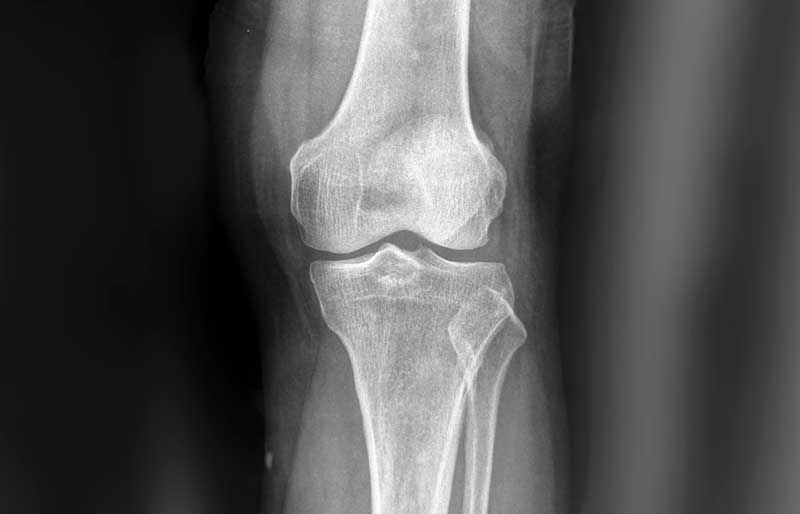

Osteoartritis (penipisan tulang rawan sendi) adalah suatu penyakit di mana tulang rawan mengalami kerusakan, penipisan dan akhirnya hilang sama sekali. Tulang rawan berfungsi melapisi ujung tulang pembentuk sendi agar tulang tidak saling bergesekan secara langsung, sehingga sendi dapat bergerak tanpa ham- batan dan rasa sakit. Osteoartritis adalah penyebab utama nyeri sendi, khususnya lutut dan panggul, pada orang berusia di atas 45 tahun. Osteoartritis sama sekali berbeda dengan osteoporosis (keropos tulang).

Kerusakan dan penipisan tulang rawan memicu terjadinya proses peradangan sendi (melalui terbentuknya beberapa zat kimia tertentu di dalam sendi), sehingga sendi terasa nyeri dan kadang-kadang membengkak. Jika penipisan semakin berat sehingga tulang rawan hilang sama sekali, maka ujung tulang pembentuk sendi saling bergesekan secara langsung sehingga menimbulkan rasa nyeri yang berat dan gangguan mekanis berupa bunyi “krek-krek” dan sendi menjadi kaku.